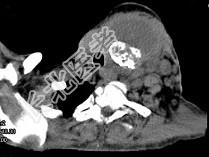

- 单项选择题女,64岁, 发现双甲状腺肿大1月余,CT如图所示, 最可能诊断是 ( )

A、甲状腺腺瘤

B、结节性甲状腺肿

C、甲状腺结核

D、甲状腺癌并淋巴结转移

E、甲状腺转移瘤